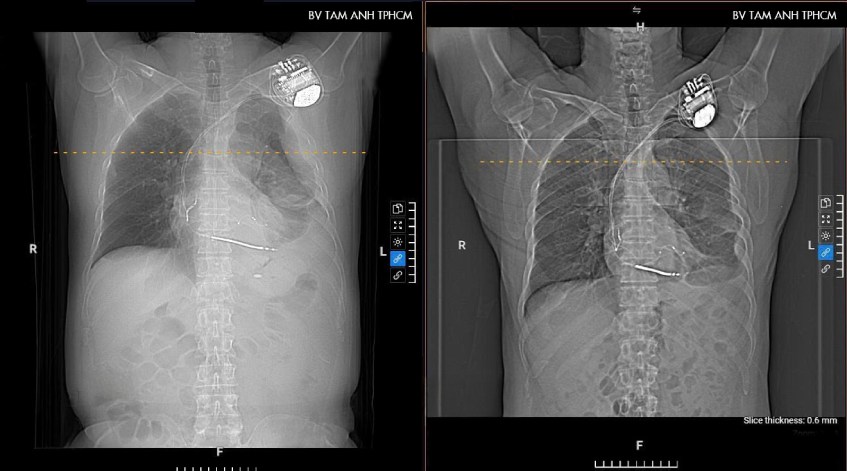

Kết quả chụp CT đa lát cắt cho thấy ông Pirone bị tràn dịch màng phổi bên trái, dịch khu trú từng ổ. Đây là tình trạng tích tụ dịch bất thường trong khoang màng phổi, nguyên nhân thường gặp là nhiễm trùng do viêm phổi, lao màng phổi, nhiễm vi khuẩn, virus, nấm. “Tuy nhiên cũng không loại trừ ung thư phổi di căn màng phổi, do đó người bệnh cần làm các xét nghiệm tiếp theo để chẩn đoán”, bác sĩ Mai Khuê cho biết.

Ông Pirone được chỉ định làm thêm xét nghiệm cấy đàm và PCR đa tác nhân, chọc dịch màng phổi xét nghiệm tế bào, sinh hóa, vi sinh. Kết quả xác định tràn dịch màng phổi là dịch viêm cấp tính, không tế bào ác tính – là biến chứng của viêm phổi, do vi khuẩn tụ cầu vàng gây ra. Ngoài ra, người bệnh còn mắc các bệnh lý rối loạn nhịp tim, suy tim khá nặng và đang điều trị bằng thuốc.

Sau 20 ngày điều trị tích cực, tình trạng bệnh được cải thiện rõ rệt, dịch ở phổi được cải thiện nhiều, ông Pirone được xuất viện sau đó. Tái khám sau một tuần, người bệnh được siêu âm, chụp X-quang kiểm tra lại, lượng dịch cải thiện gần như hoàn toàn, không còn triệu chứng đau tức ngực, khò khè, hết ho đàm.